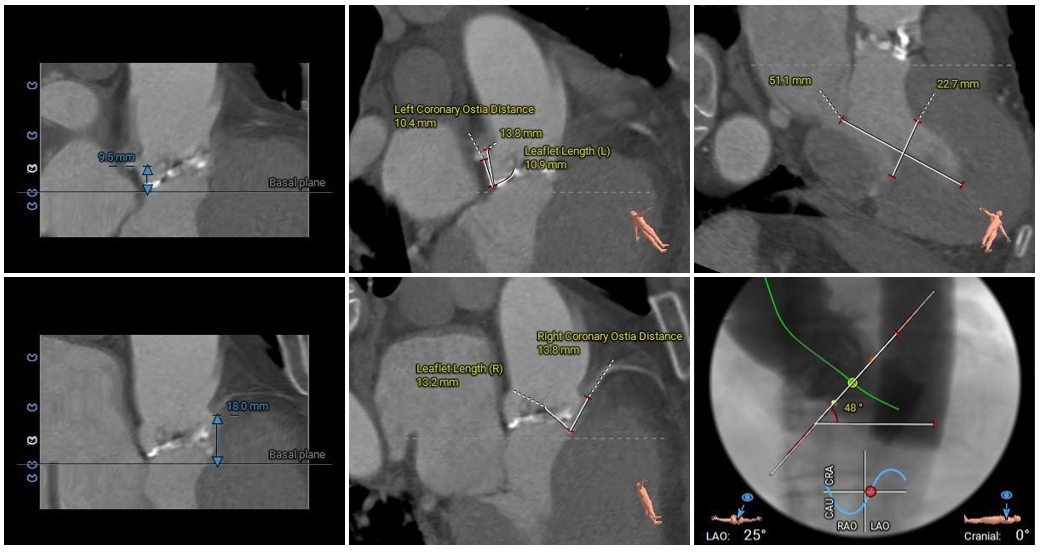

预装TaurusEliteAV23瓣膜,输送系统顺利过弓、跨瓣,于瓣环平面0mm定位释放。

瓣膜过弓跨瓣

瓣膜定位

释放到工作位后瓣膜流入端压缩明显,位置良好,冠脉血流灌注正常,脱钩释放后瓣膜位置良好,形态欠佳。

工作位造影

脱钩后造影

考虑冠脉阻挡风险较高,予以18mm球囊后扩,最终瓣膜形态、位置良好,冠脉血流灌注正常,弓部造影未见异常。

球囊后扩

最终造影